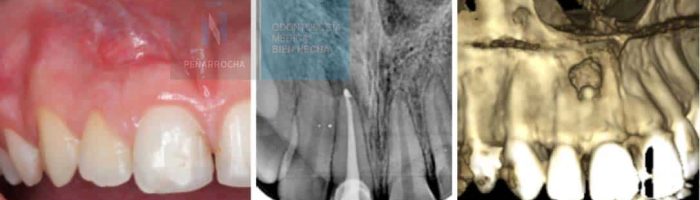

También se considera una cirugía bucal la cirugía periapical. Esta cirugía se realiza en casos de fracaso de una endodoncia. Antes de extraer un diente endodonciado que vuelve a presentar infección en muchas ocasiones puede realizarse una cirugía periapical para acceder a eliminar directamente la infección, y dar una nueva oportunidad a este diente.

María Ros nos cuenta su experiencia tras someterse a un tratamiento de cirugía periapical en nuestra clínica odontológica en Valencia.

“Gracias al Dr. Peñarrocha decidí hacerme la cirugía periapical y a raíz de ahí fue todo fenomenal. En IDIM te sientes como en casa”.